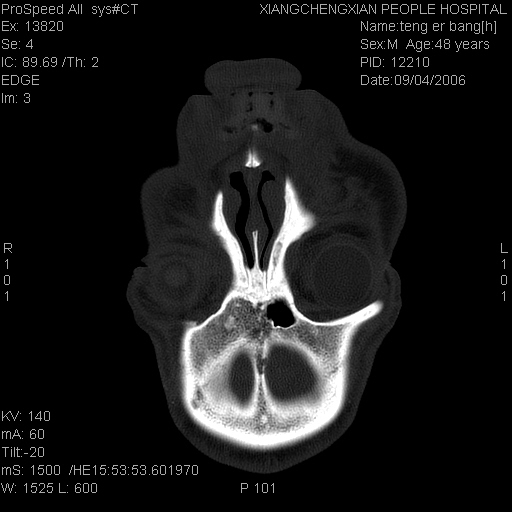

患者,男,以头面部外伤后头疼1小时为主诉入院,患者1小时前被他人打伤头部及左侧面部,眼睑无水肿,左侧面部肿胀压疼,未触及骨擦音。专科检查:耳鼻喉未见异常。

ct:平扫+冠扫:双侧鼻骨对比,冠扫s6#示右侧鼻骨尖部可见线状低密度影,边缘光滑,并见硬化.软组织未见肿胀.

诊断意见:鼻额缝(鼻骨与上颌骨额突缝),但个别同志认为是骨折.因此请同行们会诊.多谢了!

正常鼻颌缝。软组织无肿胀。鼻腔无积液积血。鼻骨光滑规整无中断。均不支持骨折。

正常鼻颌缝。软组织无肿胀。鼻腔无积液积血。鼻骨光滑规整双侧对称。均不支持骨折。